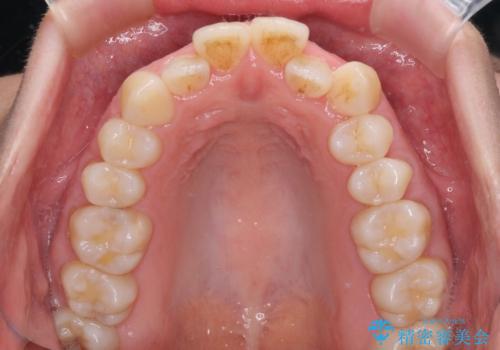

- 受け口傾向でクロスバイトの前歯を治したいとのことで来院された患者様です。

下顎骨が若干左側に変位していたため、右側にアンカースクリューを使用し、積極的に移動させながらインビザラインにて矯正治療を行うこととしました。

インビザラインによる矯正治療は、受け口傾向の治療に非常に適した方法であり、事前にシミュレーションに沿って治療を進めることできます。

今回の治療では骨格的な偏位があったためアンカースクリューを使用し、より確率の高い治療を行うことができました。